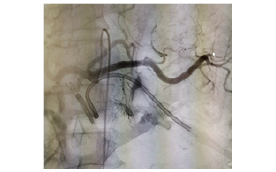

1. Opening of occluded brain vesselby putting small pipe from leg vessel

Mechanical thrombectomy is the treatment of choice within six hours of the onset of symptoms for anterior circulation stroke, and 24 hours for posterior circulation stroke. However, with latest trials, emphasis has been given for the perfusion mismatch and penumbra to core ratio and the mechanical thrombectomy can be carried out up to 24 hours in favorable conditions. These devices can be used in the larger arteries, where the caliber of the cerebral vessel is 2-5 mm, utilizing catheters to deliver a clot-disrupting or retrieval device to the occluding thromboembolus that is occluding a cerebral artery. Removal of clot by such mechanical thrombectomy devices, in contrast to pharmacological thrombolytics, can be done in a matter of minutes, thus increasing the speed of recanalization and decreasing the chance of more tissue ischemia/infarct, and also reducing the chance of reperfusion injury. Since the recanalization can be done in a very short period of time, mechanical thrombectomy provides a longer time window for use, as compared to thrombolytics.

Mechanical recanalization techniques can be classified by two major approachesâproximal and distal thrombectomy. In proximal thrombectomy, the microcatheter is placed in proximity to the site of occlusion and manual suction thrombectomy is performed by advancing an aspiration catheter at the proximal surface of the thrombus, which is retrieved once manual aspiration is applied under constant negative pressure.

On the other hand, in distal thrombectomy, the occlusion site is crossed over by using a microcatheter. Stent retrievers, which are stent-like thrombectomy devices, are used to remove the clot. This device helps in immediate flow restoration to the distal segments by deployment of the stent even before the clot is removed, thus even faster tissue reperfusion, followed by the clot removal. At the end of the procedure, the stent is removed, thereby avoiding the complications of permanent stent implantation, such as increased haemorrhagic risks giving rise to due need for double anti-platelet medication and the risk of in-stent thrombosis or stenosis.